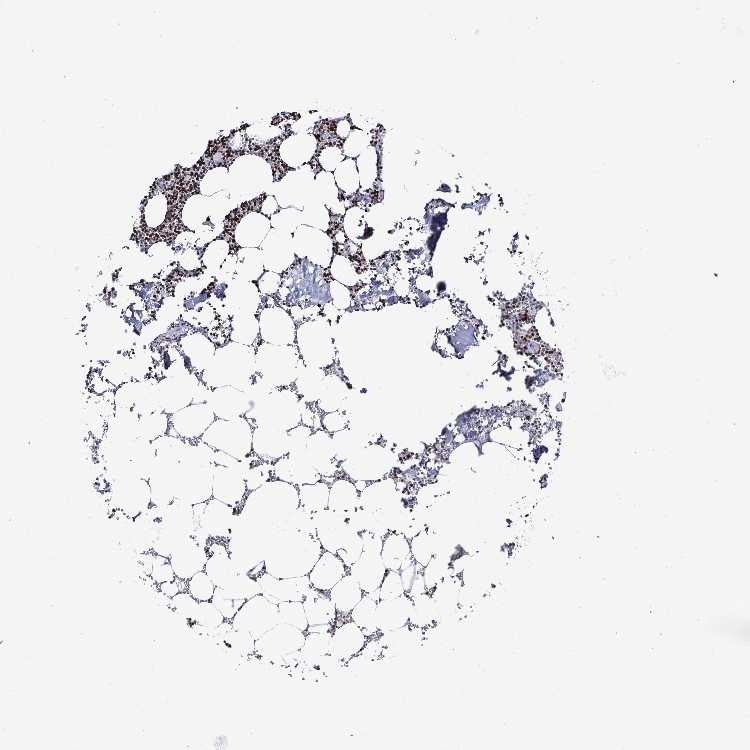

BONE MARROW - Antibody stainingi

Antibody staining in the annotated cell types in the current human tissue is reported as not detected, low, medium, or high, based on conventional immunohistochemistry profiling in selected tissues. This score is based on the combination of the staining intensity and fraction of stained cells.

Each image is clickable and will lead to virtual microscopy that enables deeper exploration of all samples and also displays staining intensity scores, fraction scores and subcellular localization as well as patient and tissue information for each sample.

Antibody HPA059098

Hematopoietic cells High